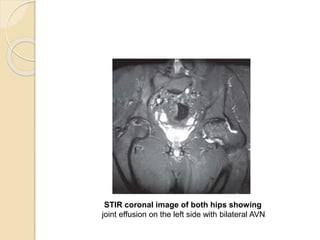

STIR coronal image of both hips showing

joint effusion on the left side with bilateral AVN

STIR coronal imageof both hips showing joint effusion on the left side with bilateral AVN